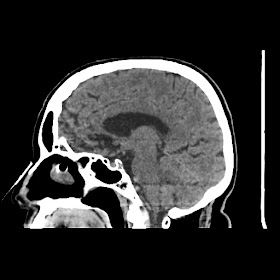

A 75 years old woman with DM-2 since 3 years

Patient O/E images:

C/O: Breathlessness X 2-3 day's

H/O: unconsiouness since few hour's at home around 10:30 pm

K/C: DM / HTN since 2-3 year's